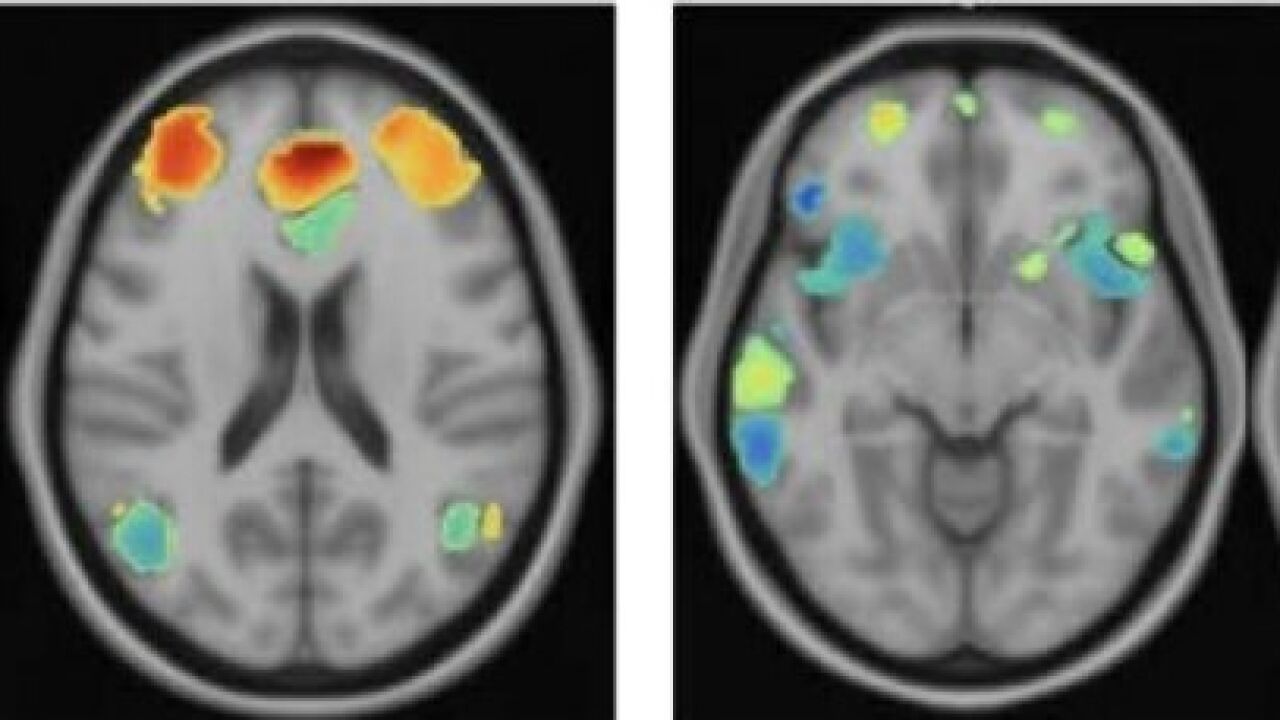

Los resultados fueron sorprendentes. Tras las 20 sesiones, aproximadamente dos tercios de los pacientes mostraron una mejoría clínica significativa, reduciendo notablemente los síntomas de depresión. Pero lo más interesante sucedió a nivel cerebral: **las imágenes de resonancia revelaron un aumento en el volumen de materia gris en dos regiones clave para la gestión emocional**: la amígdala izquierda y el [hipocampo](/neurociencias/hipocampo) anterior derecho.

La amígdala actúa como un sistema de alarma emocional, procesando el miedo, la ira y otras emociones intensas. El hipocampo, por su parte, participa en la consolidación de recuerdos y la regulación de respuestas emocionales. Un aumento en estas estructuras sugiere que **la terapia no solo ayuda a reinterpretar las emociones, sino que podría restaurar circuitos neuronales deteriorados por la depresión**.

Curiosamente, los investigadores también detectaron una disminución del volumen de materia gris en otra parte del hipocampo, su región posterior, más vinculada a funciones cognitivas como la memoria espacial. Aunque este hallazgo fue inesperado, los autores proponen que podría reflejar un reajuste funcional del cerebro tras el tratamiento, más que una pérdida patológica.